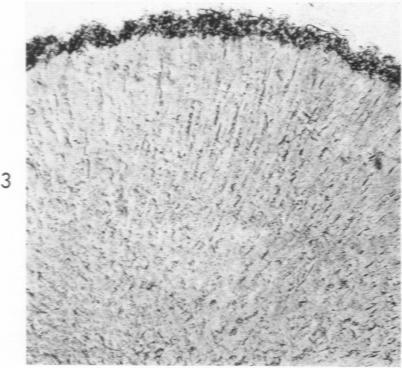

The effect of rubidium on the adrenal cortex of normal and potassium-deficient rats.

Am J Pathol. 1961 Jan;38(1):103-17.